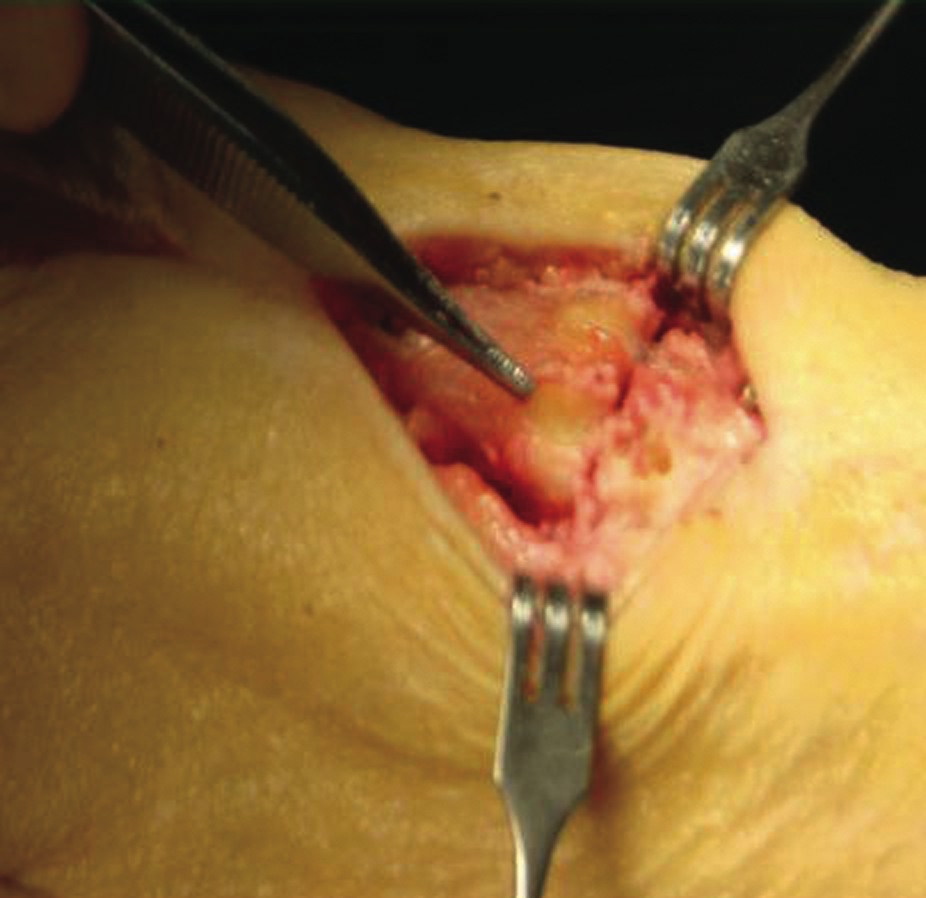

One should place the patient into a supine position and utilize a tourniquet. Evaluate post-anesthesia assessment of the first MPJ range of motion. Manually distract the first MPJ and plantarflex the first metatarsal. Dorsiflex the hallux to determine the obtainable first MPJ range of motion and evaluate for crepitus. If there is first ray hypermobility and no crepitus, one may be able to salvage the first MPJ by translating the first ray plantarly and stabilizing the medial column. Initially, surgeons should address contributing global pathology. Then proceed to the first ray and make a dorsomedial skin incision spanning the first MPJ. Retract the neurovascular structures. Make a longitudinal incision to bone, spanning the distal one-third of the first metatarsal and proximal one-half of the proximal phalanx. Evaluate the adjacent cartilage and make a critical decision to preserve or destroy the joint. It is important to realize that evaluation of cartilage quantity and quality via direct intraoperative visualization weighs heavily upon the final decision to perform a joint preservation or destructive procedure. One should strongly consider joint destructive procedures if greater than 30 percent of the dorsal portion of the first metatarsal head presents as grade III to grade IV chrondromalacia. One must independently evaluate grade III and IV chrondromalacia and osteochondral defects in the remaining 70 percent of the metatarsal head. Small cartilage lesions may yield themselves to debridement, drilling or OATS procedures whereas large cartilage defects will likely result in arthrodesis. If the joint is salvageable and one identifies first metatarsocuneiform hypermobility, perform a cheilectomy and a subsequent, sagittal Lapidus procedure. If one identifies hypermobility or posttraumatic first metatarsal angular pathology, correct it after completing the first MPJ soft tissue and osteophyte debridement. If one decides to perform arthrodesis on the joint, debride identified osteophytes, loose bodies, synovitis and scar tissue. Denude the adjacent cartilaginous surfaces to the healthy level of bleeding bone via curettage or via convex distal and concave proximal reamers. Fenestrate the adjacent bone surfaces with a 1.0- or 1.5-mm drill bit. Temporarily fixate the hallux by utilizing two K-wires in the desired position. The position should be approximately 20 to 30 degrees dorsiflexed in relation to the first metatarsal declination; abducted and parallel to the second digit; and with the nail void of frontal plane varus or valgus rotation. Obtain an AP radiograph to evaluate the bony apposition and alignment of the proposed first MPJ arthrodesis. Also obtain a lateral radiograph with the foot loaded in order to evaluate the hallux and its relationship to the first ray. After obtaining the desired position, utilize two fully threaded (3.5 or 4.0) crossing cortical screws for permanent fixation. Place the first screw from proximal medial to distal lateral and place the second screw from distal medial to proximal lateral across the first MPJ. Ensure the screws do not cross at the level of the joint. Use a 3.5-mm burr to create a dell in the cortical bone where the head of the screws engage the bone as Manloli and Hansen have described.48 After obtaining rigid internal fixation across the first MPJ, utilize a shear strain autograft (harvested via a percutaneous calcaneal grafting technique) at the arthrodesis site.57 Place the autograft in two troughs created by the 3.5-mm burr at the arthrodesis site. Use a bone mallet and tamp to provide a press fit.58